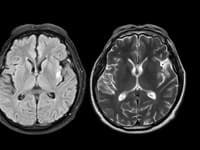

Ilustračný obrázok Zobraziť galériu (3)

(Zdroj: Getty Images)